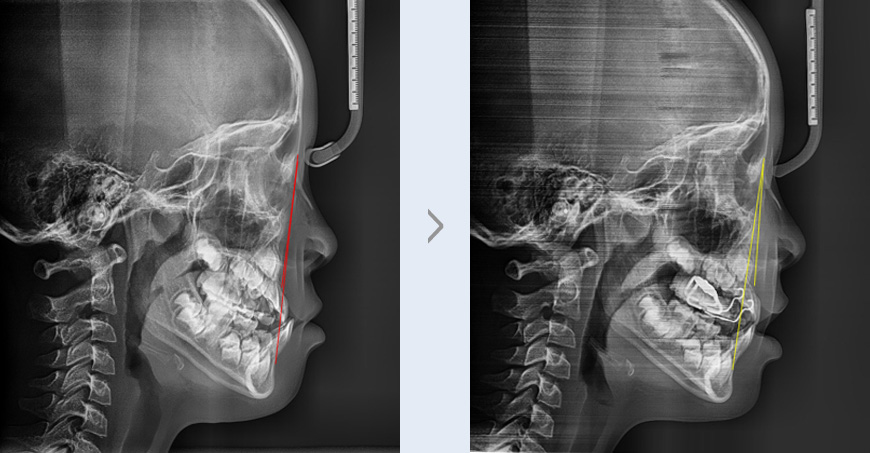

위쪽 앞니가 나오지 않고 윗니와 아랫니가 거꾸로 물리는 증상으로 내원한 초등학교 1학년 여학생입니다.

진단 결과 위쪽 앞니가 결손 되어 있고 위턱의 공간이 좁은 상태이며 위턱의 성장이 부족한 주걱턱(골격성

3급 부정교합) 증상으로 확인하였습니다.

아랫니가 윗니보다 바깥쪽에 위치한 반대교합을 개선하고 정상적인 턱뼈 발육을 유도하기 위해 RPE를

착용하여 위턱 공간을 넓히는 치료와 위턱을 앞으로 이동시키기 위한 페이스마스크 착용을

병행하였습니다.

위턱 공간을 확보하여 결손된 앞니가 정상적인 위치에 나올 수 있도록 유도했고, 상대적으로 성장이

부족했던 위턱의 발육을 촉진하여 아래턱과 제대로 맞물릴 수 있게 되었습니다. 그 결과 치아의 앞니의

심미적인 부분은 물론 음식물을 제대로 씹을 수 있는 기능적인 부분까지 개선되었습니다.